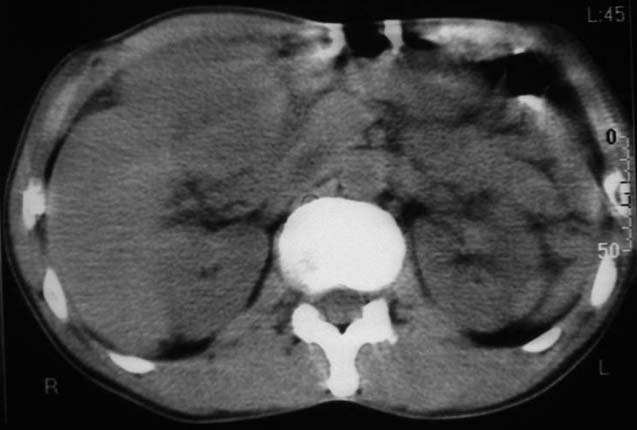

男,50y,右上腹包块痛10天,查:右上腹饱满,右肋下触及6*6cm大小包块,质硬,压痛。患者诉:10天前感冒胸闷,痛,后痛及右上腹部,既往有肝炎病史。

没有增强!只能考虑左叶内侧段巨块型肝癌(外生型)可能性大;胆囊呢?不除外胆囊癌累及肝脏。

病变位于胆囊窝内,其内密度不均,肝总管及胆总管扩张,胃里面没有清水充盈,不解为什么楼主不做好了准备再做呢,支持:“左叶内侧段巨块型肝癌(外生型)可能性大;不除外胆囊癌累及肝脏”建议增强吧。

考虑:肝左内叶巨块型癌,主动脉旁淋巴结转移.(有一层面似见胆囊受压.)